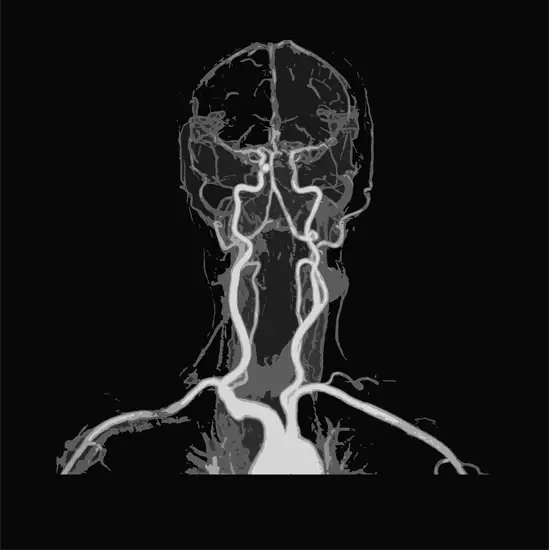

MR angiography of neck vessels is a test to detect the narrowing of blood vessels in the neck. This imaging test creates two 3D images of blood vessels..

MRA uses a magnetic field, radio waves, and a computer to produce images of soft tissues, bones and other internal structures of the body. MRA of the neck creates images of the blood vessels of the neck that can aid in the detection of narrowing of the arteries.

An MRA or magnetic resonance angiography is used to detect the blockages or narrowing in the arteries of the neck. The MRA process is noninvasive. The scan images produced by the MRA procedure create two or three-dimensional images of the arteries of the neck.

Magnetic Resonance Angiography (MRA) is an advanced diagnostic modality that uses radio waves and magnetism to create high-resolution images of the vessels and other related structures of the neck. This helps in the atraumatically study of vascular structures.. Its basic principles are reported in the present paper, together with the results of a preliminary study of normal neck anatomy.